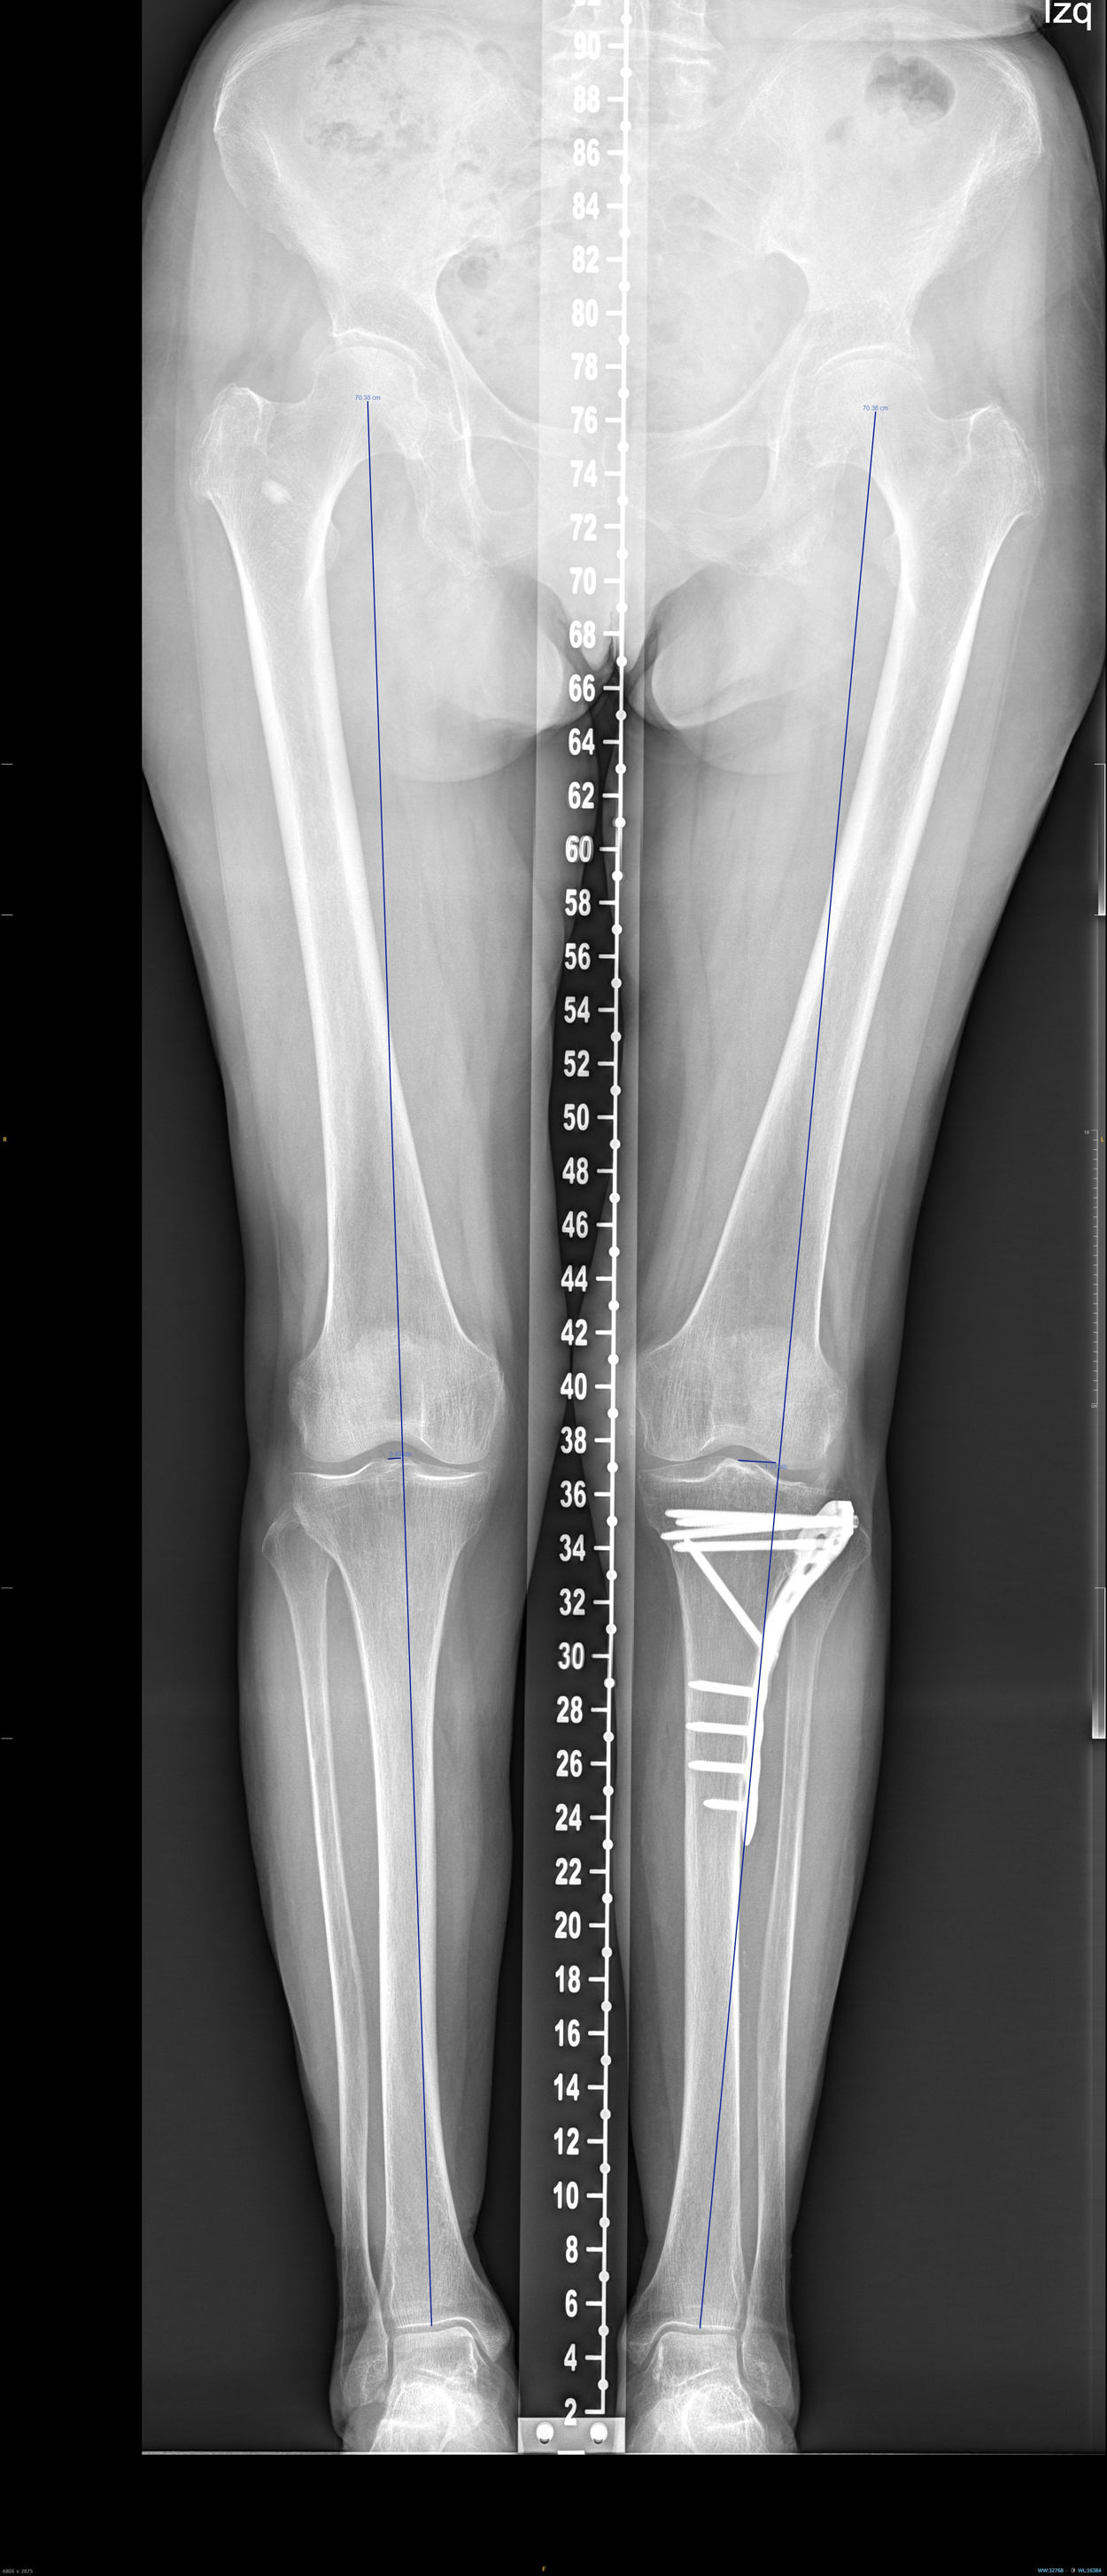

Deviation in millimetres of the load axis relative to the contralateral limb, the medial proximal tibial angle (MPTA) of both limbs, and the difference in degrees between them were analysed using telemetry (Fig. 2).

In the teleradiology analysis, the difference in the mean axis deviation from the contralateral leg was 12mm. The mean difference in MPTA was −1.1 degrees.